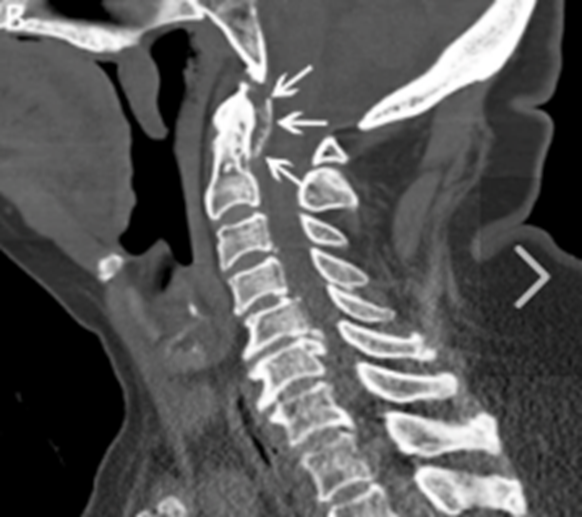

石灰沈着性頸長筋腱炎』についていしい内科・胃大腸内視鏡・IBDクリニック。

石灰沈着性頸長筋腱炎関節痛・筋肉痛と内科の病気 - みやけ内科・循環器科 総合内科のアプローチ。